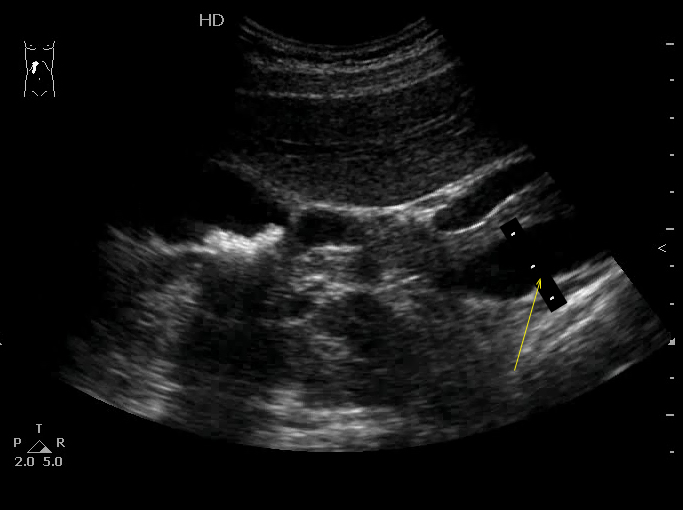

УЗИ ЖВП: конкремент в пузырном протоке

Молодая женщина, плановое обследование.

Жалоб не предъявляет.

ЖКБ, холецистолитиаз, необструктивный конкремент пузырного протока.

Оперирована, все подтвердилось.

Да, холедох где то до 7-8 мм. - верхняя граница нормы.

Камни в пузырном протоке четко видны.